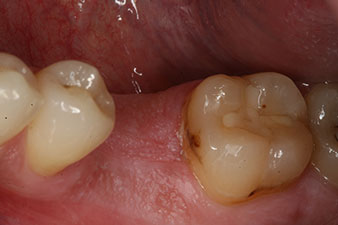

Initial clinical situation

Fig. 1: Initial clinical situation after healing of extraction alveolus 36: The bone base is wide and there is sufficient keratinized gingiva.

A 28-year-old patient with a history of heavy smoking had to have tooth 36 extracted as a result of recurring apical periodontitis.

Due to the generally intact neighbouring teeth the only way to fill the gap was an implant.